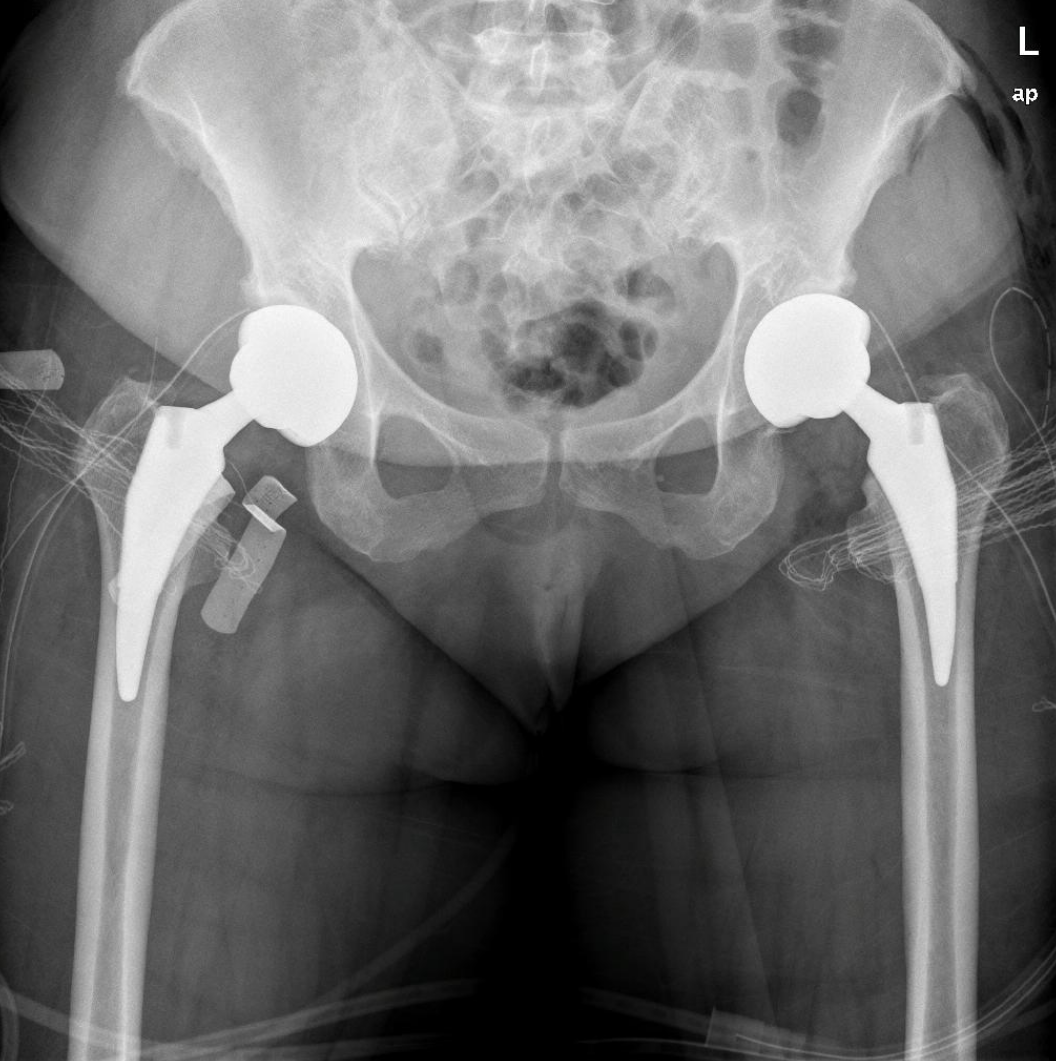

Το πρώτο βήμα κατά τη λήψη της απόφασης για την αντικατάσταση ισχίου είναι να συναντήσετε τον χειρουργό σας για να δείτε εάν είστε υποψήφιος για χειρουργική επέμβαση ολικής αρθροπλαστικής ισχίου. Ο χειρουργός σας θα πάρει το ιατρικό ιστορικό σας, θα κάνει μια φυσική εξέταση και θα ζητήσει ακτινογραφία του ισχίου σας. Ακόμα κι αν ο πόνος είναι έντονος και οι ακτινογραφίες δείχνουν προχωρημένη αρθρίτιδα της άρθρωσης, η πρώτη γραμμή θεραπείας είναι σχεδόν πάντα μη χειρουργική. Αυτό περιλαμβάνει απώλεια βάρους εάν χρειάζεται, πρόγραμμα άσκησης, αντιφλεγμονώδη φάρμακα, ενέσεις ή νάρθηκες. Εάν τα συμπτώματα συνεχιστούν παρά αυτές τις θεραπείες και με επιβεβαιωτικές ακτινογραφίες, τότε μπορείτε να εξετάσετε το ενδεχόμενο χειρουργικής επέμβασης.

Τα περισσότερα εμφυτεύματα σήμερα έχουν παρόμοια σχέδια και σχήματα, αλλά ο γιατρός σας θα καθορίσει ποια σχέδια λειτουργούν καλύτερα για το σώμα σας. Αυτά τα εμφυτεύματα είναι κατασκευασμένα από κοβάλτιο χρώμιο ή τιτάνιο. Μια μεταβλητή που παραμένει ακόμα είναι η επιφάνεια φόρτισης. Η επιφάνεια φόρτισης είναι η σφαίρα, η κεφαλή και η επένδυση που προσκολλώνται στο μηριαίο στέλεχος, και το κυπέλιο, η το κοτυλιαίο εμφύτευμα που στερεώνεται στο οστό. Η κεφαλή μπορεί να αποτελείται είτε από μέταλλο (κράμα χρωμίου κοβαλτίου) είτε από κεραμικό και η επένδυση μπορεί να είναι από πλαστικό (πολυαιθυλένιο), μέταλλο ή κεραμικό. Η κεφαλή και η επένδυση μπορούν στη συνέχεια να χρησιμοποιηθούν σε διαφορετικούς συνδυασμούς και ονομάζονται για τον αντίστοιχο συνδυασμό επένδυσης κεφαλή (μέταλλο σε πολυ, κεραμικό σε πολυ, κεραμικό σε κεραμικό κ.λπ.).

Το 2023, τα περισσότερα χρησιμοποιούσαν επένδυση πολυαιθυλενίου με κεραμική κεφαλή, ενώ άλλοι συνδυασμοί χρησιμοποιούνται με μικρότερη συχνότητα. Μπορείτε να συζητήσετε αυτές τις διαφορές με τον χειρουργό σας για να προσδιορίσετε ποιο εμφύτευμα είναι καλύτερο για εσάς.